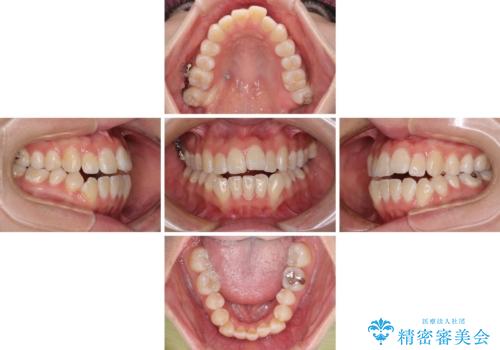

外に飛び出して磨きにくい奥歯と上下前歯の隙間 インビザラインによる矯正治療

- 上下前歯の隙間と、外側を向いていて歯磨きのしにくい奥歯を気にして来院された患者様です。

下顎前歯が1本欠損しており、上下アーチはアンバランスとなりますが、インビザラインを用いて上下の隙間を改善しながら歯列を整えることとしました。

外側を向いている奥歯は、内側にアンカースクリューを埋入して牽引の固定ゲント氏、部分的にワイヤー装置を用いることで歯列に納めることとしました。